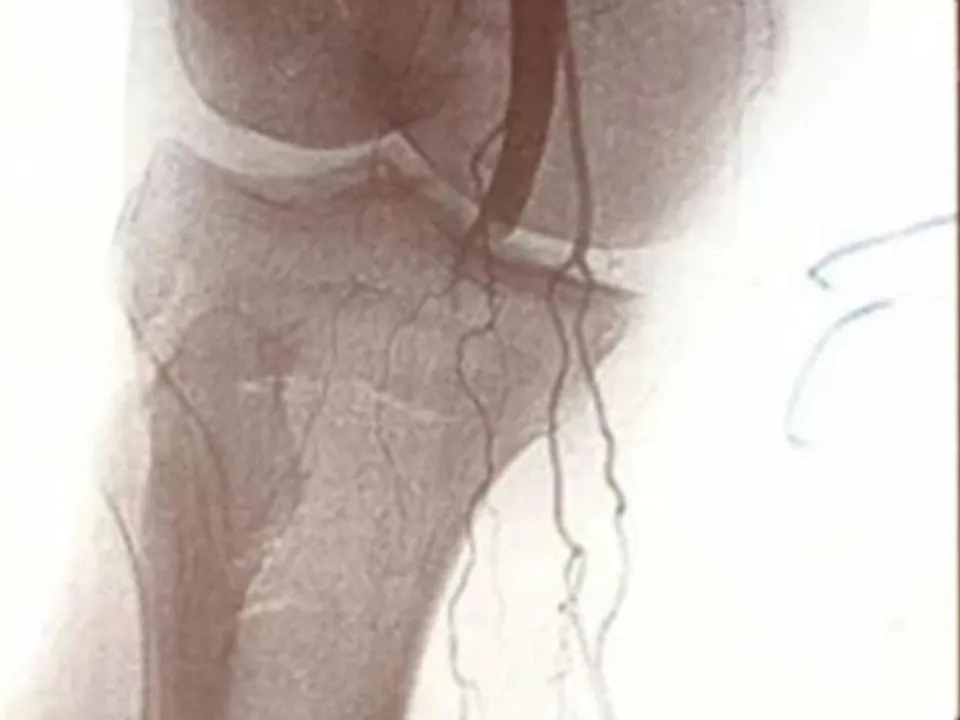

В Домодедовской больнице проводятся уникальные операции по эмболизации ветвей локтевой и подколенной артерий

Врачи травматологи-ортопеды Домодедовской больницы в сотрудничестве с эндоваскулярными хирургами успешно применяют инновационную методику лечения тяжелых заболеваний костно-двигательной системы.

Благодаря уникальным малоинвазивным операциям по эмболизации ветвей подколенной или локтевой артерии, проведенным на современном медицинском оборудовании, пациенты навсегда избавляются от мучительных болей и возвращаются к активной жизни.